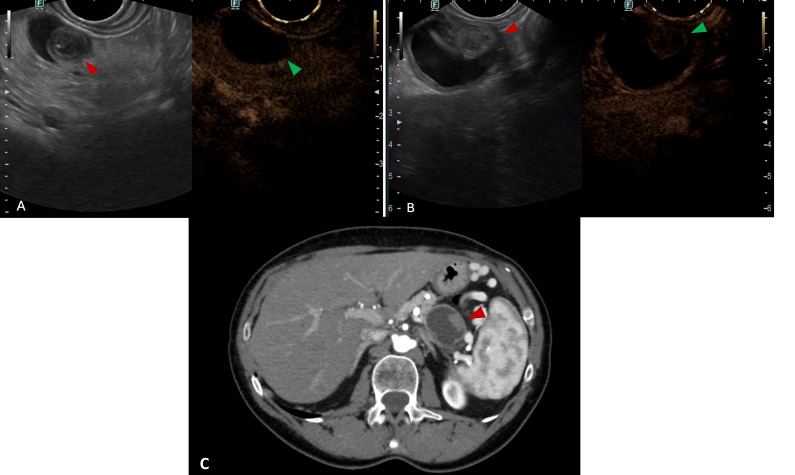

近年来,偶发性胰腺囊性病变(PCLs)的发病率有所上升,这主要是由于成像技术的进步和使用的增加。内镜超声(EUS)已成为评估和表征pcl的重要工具,可以进行详细的形态学评估,并有助于识别进展为高级别不典型增生或浸润性胰腺癌的高风险病变。本综述旨在概述EUS在pcl评估中的关键方面,涵盖了从形态学评估和对比度增强成像到弹性成像,细针穿刺生物标志物分析,细胞学,DNA测序,组织学评估以及共聚焦激光内镜或人工智能的新兴作用的一系列模式。此外,我们还讨论了pcl的EUS治疗方式,目前EUS的局限性,预期的技术进步以及领先科学学会推荐的pcl临床处理的多种管理策略。

The incidence of incidental pancreatic cystic lesions (PCLs) has risen in recent years, largely due to advances in and increased use of imaging techniques. Endoscopic ultrasound (EUS) has become a crucial tool for evaluating and characterising PCLs, allowing for detailed morphological assessment and aiding in the identification of lesions with a higher risk of progression to high-grade dysplasia or invasive pancreatic carcinoma. This review aims to outline the key aspects of EUS in the evaluation of PCLs, covering a range of modalities from morphological assessment and contrast-enhanced imaging to elastography, fine-needle aspiration for biomarker analysis, cytology, DNA sequencing, histological evaluation and the emerging role of confocal laser endomicroscopy or artificial intelligence. Additionally, we address therapeutic EUS modalities for PCLs, the current limitations of EUS, anticipated technological advancements and the diverse management strategies recommended by leading scientific societies for the clinical handling of PCLs.